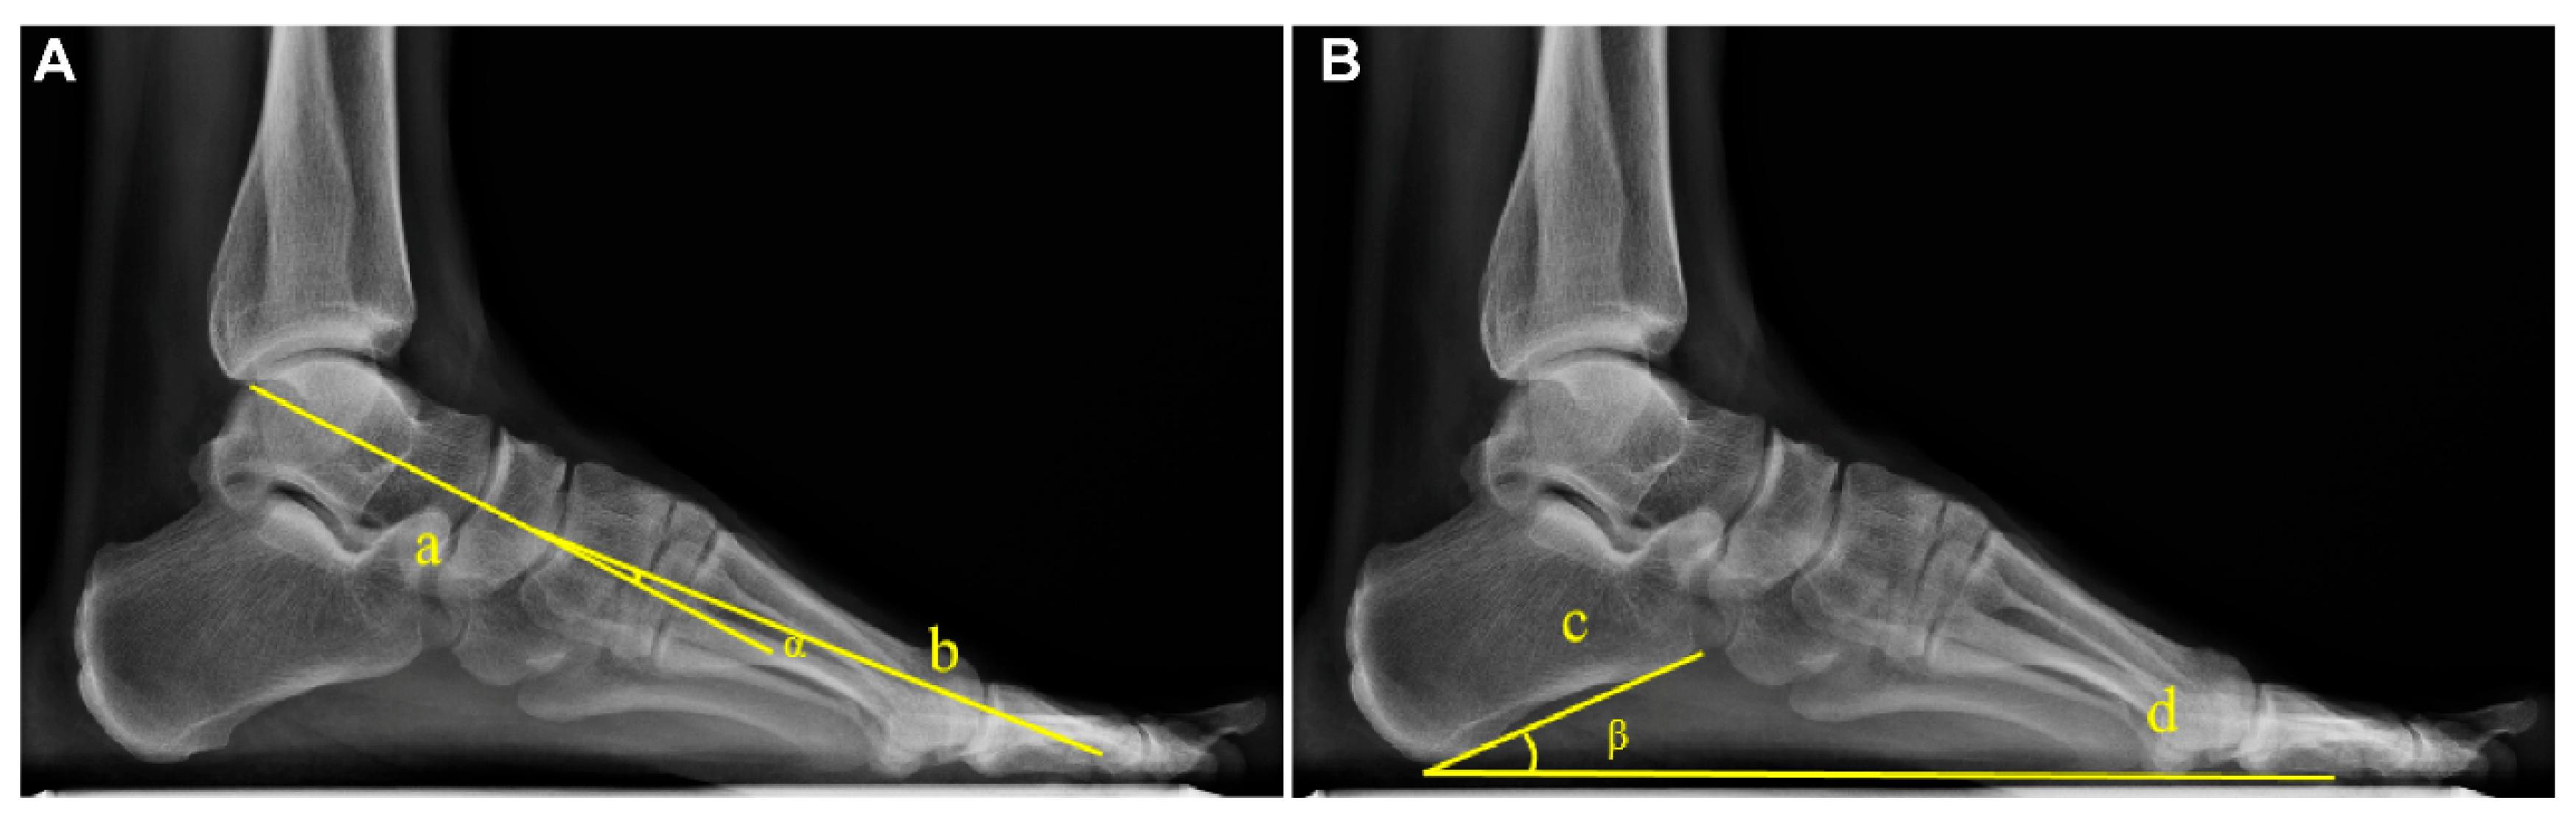

The Meary angle was measured as the angle between the longitudinal axis of the talus and the longitudinal axis of the first metatarsal, with a normal range of 0° ± 4° [11,18]. The Pitch angle was defined as the angle between the inferior border of the calcaneus and the horizontal line, with a normal range of 20–30°. The measurements are exemplified in Figure 1.

Figure 1.

Example diagram of arch angle measurement based on WB X-rays. (A) The Meary angle (α): formed by the longitudinal axis of the talus (Line a) and the longitudinal axis of the first metatarsal (Line b). (B) The Pitch angle (β): formed between the tangent to the inferior border of the calcaneus (Line c) and the line connecting the lowest point of the calcaneus to the lowest point of the medial sesamoid of the forefoot (Line d).